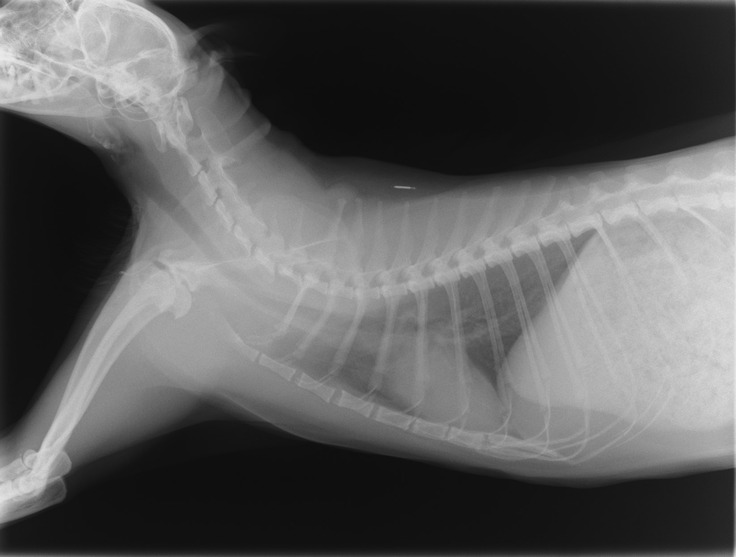

また今日はレントゲンもとりました。

肺の状態も心配だったのですが、

特に悪そうな感じもなく、ほっと一安心しました。